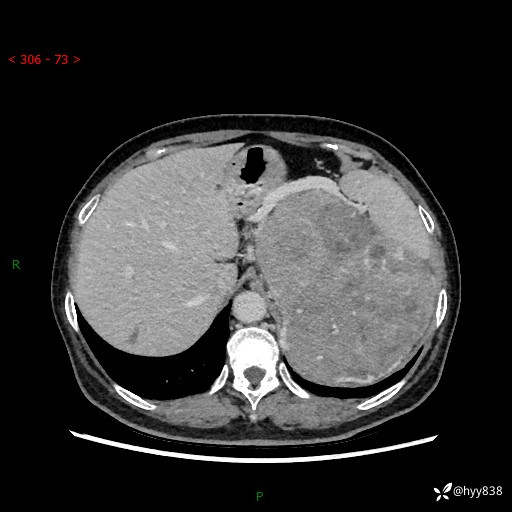

据说只有腹膜后,才能见到如此巨大的肿块---(有结果)

主诉:发现腹膜后占位1周

简要病史:患者1周前因头晕在当地第二人民医院检查发现左侧腹膜后区巨大富血供占位性病变,患者自诉腹部稍硬,无其他不适,无血尿,无腰痛等不适,患者为求进一步治疗来我院,门诊以“腹膜后占位性病变”收入我科。 起病以来,患者精神、饮食、睡眠可,大便正常,小便如上述,体力体重无明显改变。

临床诊断:腹膜后占位

腹部CT增强(动脉期+静脉期 ) ---平扫外院